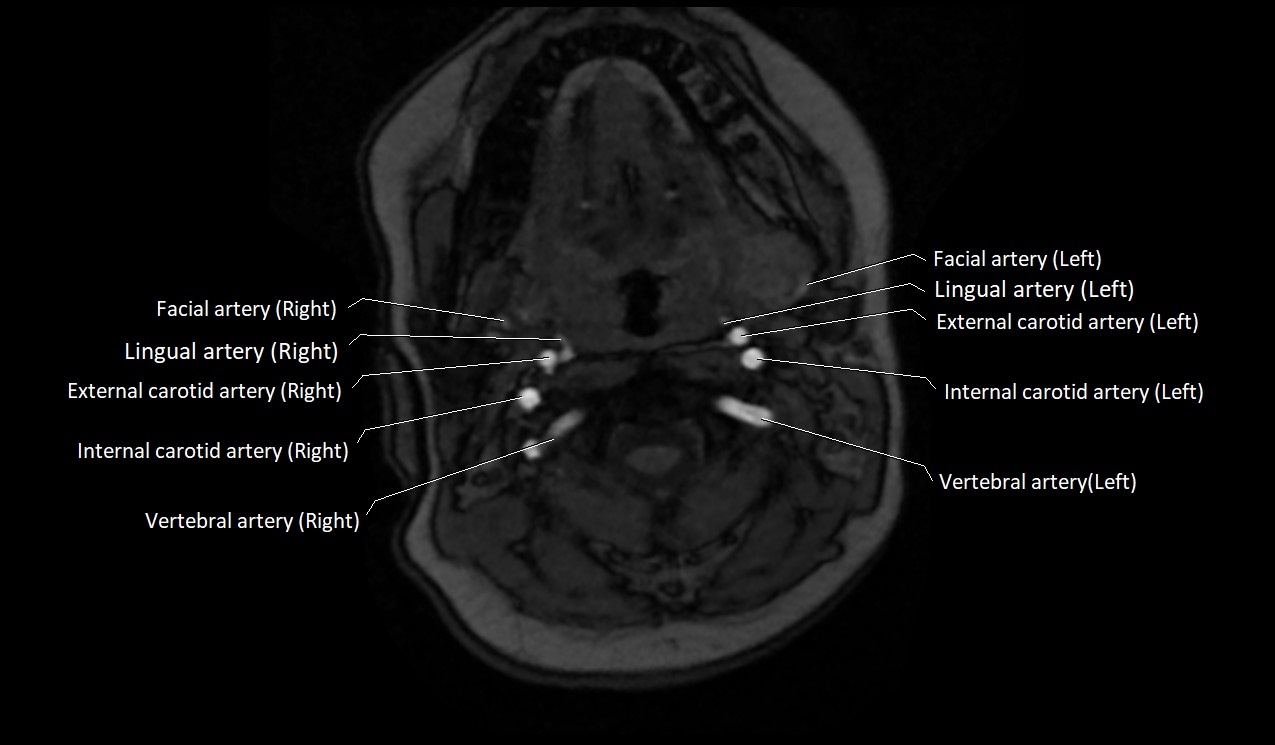

MRI images

image